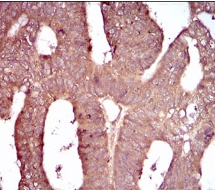

IHC    1/200 - 1/1000